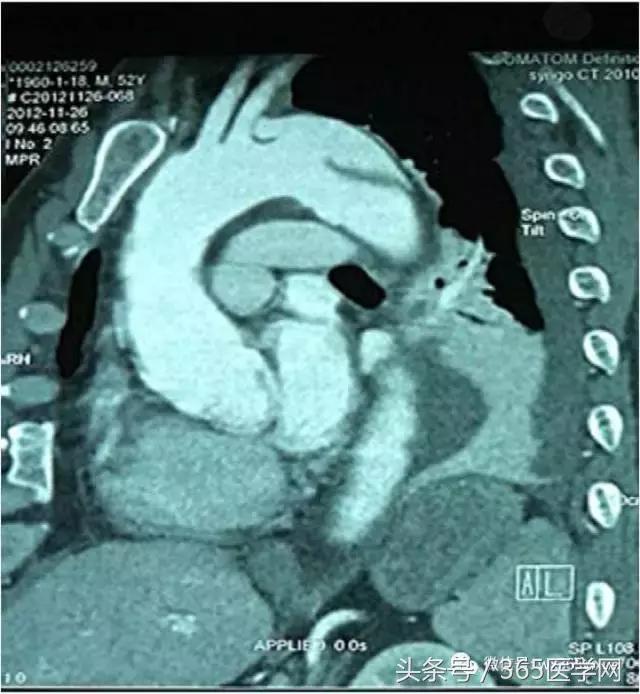

2.形态学复杂:短瘤颈(图1B)(<15mm)、锥形瘤颈、瘤颈夹角>60°、II/III型弓(图1C)(以Myla分型为准,主动脉弓顶至头臂干开口垂直距离小于左颈总动脉直径为Ⅰ型弓,垂直距离为直径的1~2倍为Ⅱ型弓,大于2倍直径为Ⅲ型弓);

在临床上我们经常碰到主动脉Ⅲ型弓(图1C),即弓部成角陡峭,容易使主动脉支架外鞘在跨弓时打折,从而使支架释放时阻力增大,严重的甚至导致释放支架时移位,造成想象不到的严重后果。这样的情况就对支架材料提出了很高的要求。我们在临床实践中发现,上海微创公司的Hercules Low Profile 直管型覆膜支架系统(图5A)比较适合主动脉弓部成角陡峭的病人。原因有三:其一,它有着目前国内最小的输送系统外径,最小能够达到18F(直径20-36mm支架);其二,它有着覆膜套管跨弓设计,整个输送系统跨弓时阻力小,柔软不易打折,并且在支架释放瞬间稳定不易移位;其三,主动脉夹层是由于动脉壁出现破口,血流冲入导致形成真腔和假腔,由于假腔的压迫真腔一般会相对缩小,形成上粗下细的锥度。传统的胸主动脉支架系统如有些品牌支架没有锥度,头到尾直径没有变化,容易在释放时对相对缩小的真腔管壁造成应力拉扯,留下再发破口的隐患,因此经常需要在后段加入限制性裸支架人为形成锥度,不仅效果得不到很好保证,而且增加了患者经济负担。Hercules Low Profile独有大锥度支架规格,支架锥度范围2-10mm,锥度变化平缓,在释放 后能够更贴壁并且不造成过多拉扯,更适合主动脉夹层患者。对于下面的病例(图5B、C),患者主动脉角度陡峭,破口位置高,就需要选择本身比较柔软、容易过弓的支架,使用微创的公司Hercules Low Profile就能达到很好的效果。

图1C 弓部成角复杂